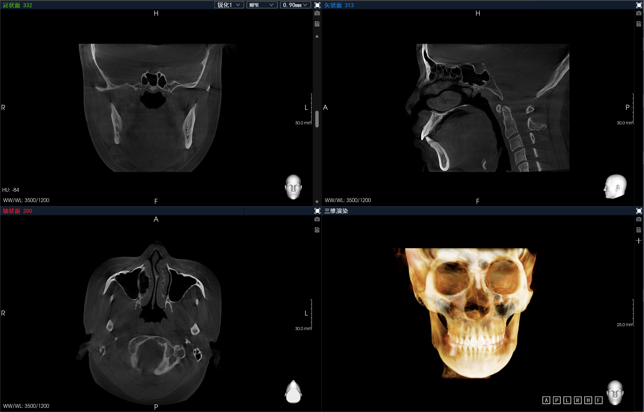

“去伪影,用博爵”,博爵(Bondream)智能口腔CBCT是博恩集团匠心智造的爆款产品,目前拥有多款型号,满足临床不同客户需求。该系列产品通过AI迭代算法,目前核心拥有准能谱金属伪影校正技术,低剂量AI降噪技术,智能3D全景技术以及多轨迹聚焦全景等,致力于为临床诊疗提供更清晰的影像和更便捷的使用感受。